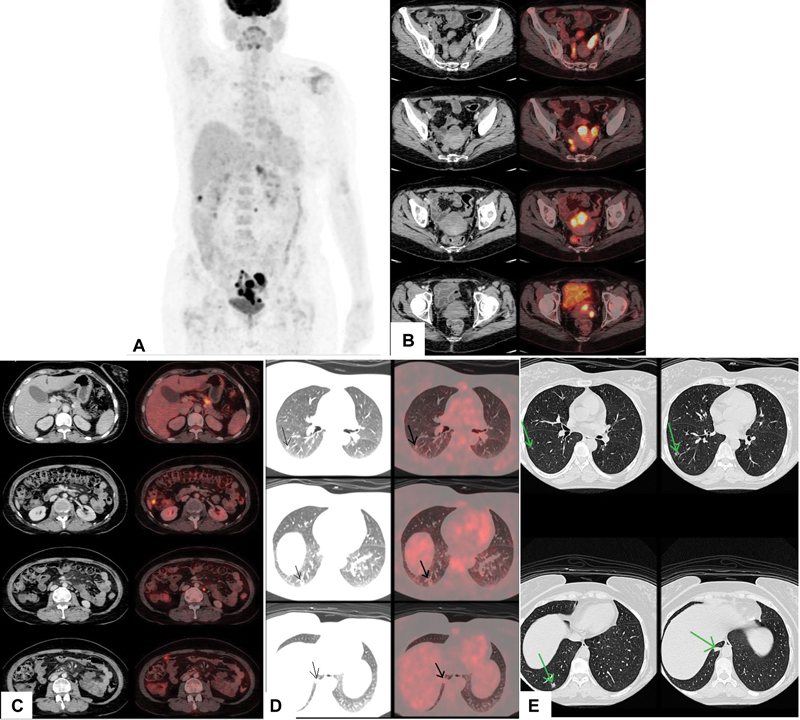

急性淋巴细胞白血病/淋巴瘤(ALL)髓外浸润到生殖器官是非常罕见的。在这里,我们报告一例无症状的49岁女性,已知的前体b细胞ALL病例,偶然发现超声增厚和异质高回声子宫内膜。磁共振造影示大息肉样增强病灶,弥散受限,占据子宫内膜腔,左侧附件、左侧卵巢、输卵管均见类似病灶,临床病史及外观不典型,怀疑白血病浸润。18 f -氟脱氧葡萄糖正电子发射断层扫描/计算机断层扫描(18 F-FDG PET/CT)显示子宫内膜腔、左附件、大网膜结节、腹膜后淋巴结、胰腺病变强烈代谢活跃,右下叶少量不规则结节。活检结果证实ALL髓外复发。因此,18f - fdg PET/CT可以作为一个很好的全身检查来寻找髓外复发部位。

Extramedullary infiltration of acute lymphoblastic leukemia/lymphoma (ALL) to genital organs is extremely rare. Here, we present a case report of an asymptomatic 49-year-old female, known case of precursor B-cell ALL, who was incidentally detected with thickened and heterogeneously hyperechoic endometrium on sonography. Contrast magnetic resonance imaging detected large polypoidal enhancing lesions showing intense diffusion restriction occupying the endometrial cavity and similar lesions in the left adnexa, left ovary, and fallopian tube which were suspicious for leukemic infiltration because of the clinical history and atypical appearance of the lesions. 18 F-fluorodeoxyglucose positron emission tomography/computed tomography ( 18 F-FDG PET/CT) was done which revealed intensely metabolically active lesion in the endometrial cavity, left adnexa, omental nodules, retroperitoneal lymph node, pancreatic lesion, and few irregular nodules in the right lower lobe. Biopsy findings confirmed extramedullary relapse of ALL. Hence, 18 F-FDG PET/CT can act as a good whole body survey to look for extramedullary sites of relapse.